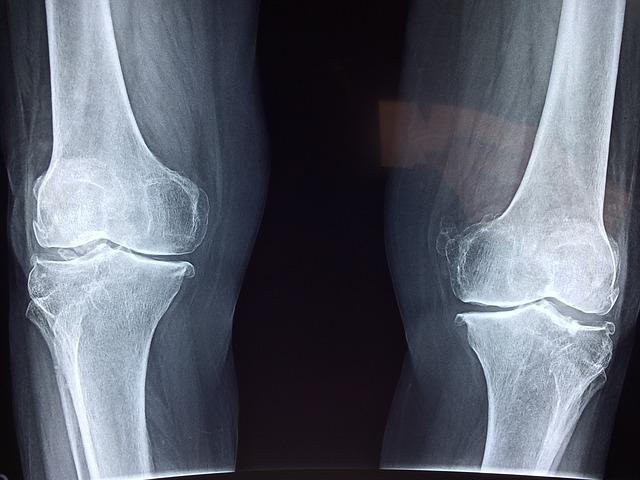

마가목 효능 - 뼈 건강, 허약체질 개선

마가목에 포함된 프로보노이드 성분은 기관지에도 좋지만 관절염에도 좋습니다. 연골 손상을 보호하며 뼈의 파괴와 노화를 억제하는 효과가 있습니다.